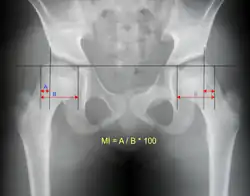

| X-ray showing a joint dislocation of the left hip. | |

An anterior-posterior (AP) X-ray of the pelvis and a cross-table lateral X-ray[24] of the effected hip are ordered for diagnosis.[4][5][16] The size of the head of the femur is then compared across both sides of the pelvis. The affected femoral head will appear larger if the dislocation is anterior, and smaller if posterior.[7] A CT scan may also be ordered to clarify the fracture pattern.[20]